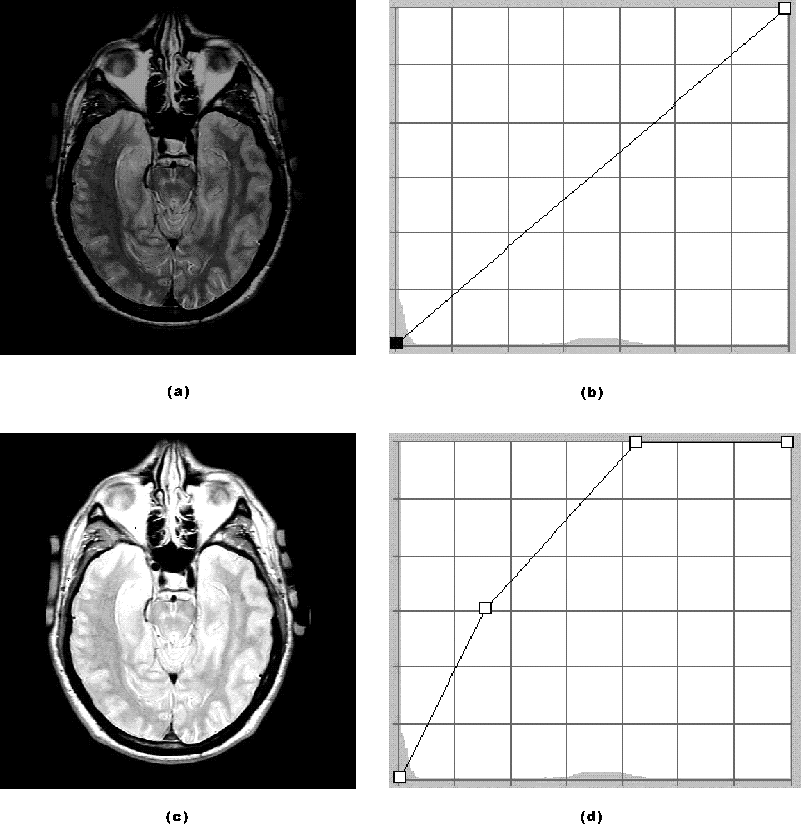

Figure 1: Applying contrast enhancement